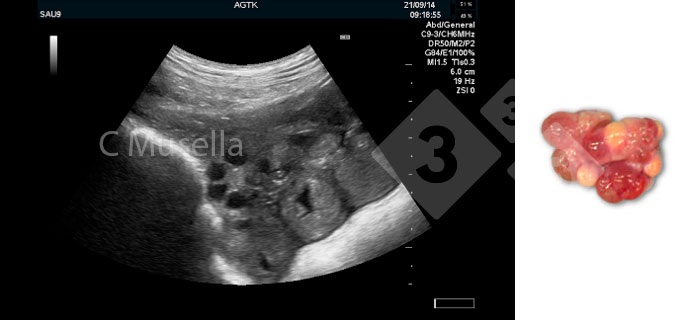

O diagnóstico de quistos ováricos únicos ou múltiplos é relativamente simples, embora a identificação completa do tipo de quisto por ecografia nem sempre seja certa.

Figura 3. Ovários poliquísticos